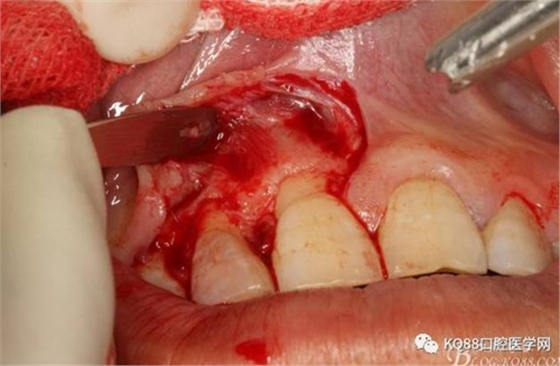

圖8.從垂直切口和水平切口的連接處翻瓣。發(fā)現(xiàn)11和12之間的骨壁有缺損。

圖9.翻開(kāi)角形瓣后,有骨壁缺損,囊壁有穿孔,這就是溢膿的竇道出口。